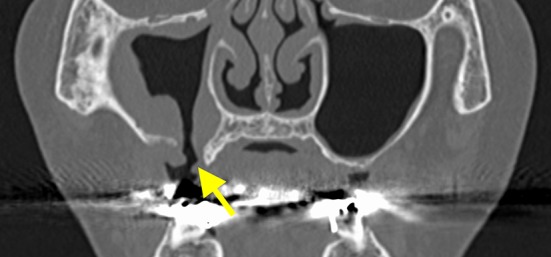

Fig. 8.

The preclosure operative coronal section computed tomography image shows right maxillary sinusitis. Hypertrophy of the consecutive mucous membrane of the maxillary sinus is detected from the fistula (the arrow indicates the fistula)